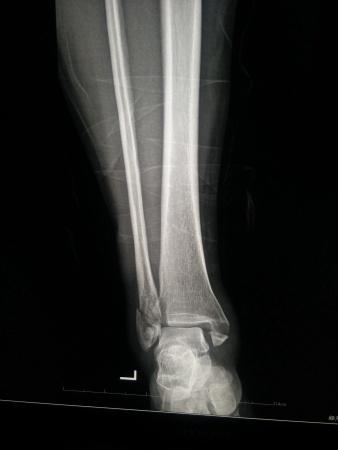

左三踝骨折手术治疗

患者女,外伤后左踝关节活动受限1小时入院,

入院后查体:左踝关节肿胀,活动受限,行DR及左踝关节CT检查,如下图,手术待肿胀消退后行手术治疗,目前愈合良好,请问问各位老师,好久可以下地呀, 下胫腓联合镙钉3个月取呀,